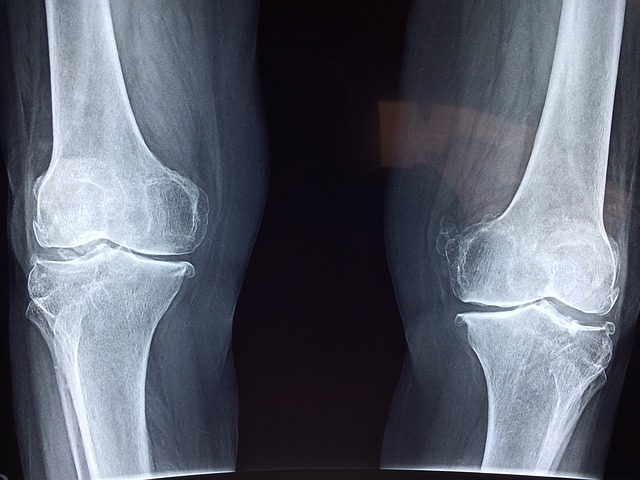

보건복지부와 노인 의료 나눔 재단에서 진행하는 노인 인공 관절 수술비 지원 사업은 무릎 관절증으로 지속적인 통증에 시달리는 사람들의 고통을 경감하고, 삶의 질을 개선하기 위해 무릎 인공 관절 수술비를 지원하는 사업입니다.

성상철 의학박사는 무릎 인공 관절 수술은 수술 2~3개월 후면 통증이 많이 없어지고 정상적인 생활이 가능해져서 환자들이 매우 만족해한다고 합니다. 최근 미국에서는 1년에 100만 명, 우리나라에서도 1년에 10만 명 정도의 퇴행성 관절염 환자가 인공 관절 수술을 받고 있으며, 대부분 연령이 65세가 넘는 분들이라고 합니다. 우리나라 의학 수준은 세계 최고의 수준으로 수술 환자의 만족도가 90~100% 가까운 안전하고 보편적인 수술이라고 하는대요. 연령이 많을수록 수술에 대한 두려움이 클 수도 있지만 큰 질병만 없으면 수술 후 회복 하는데 큰 문제가 없어 가벼운 운동이나, 사회적 활동이 가능하다고 합니다.